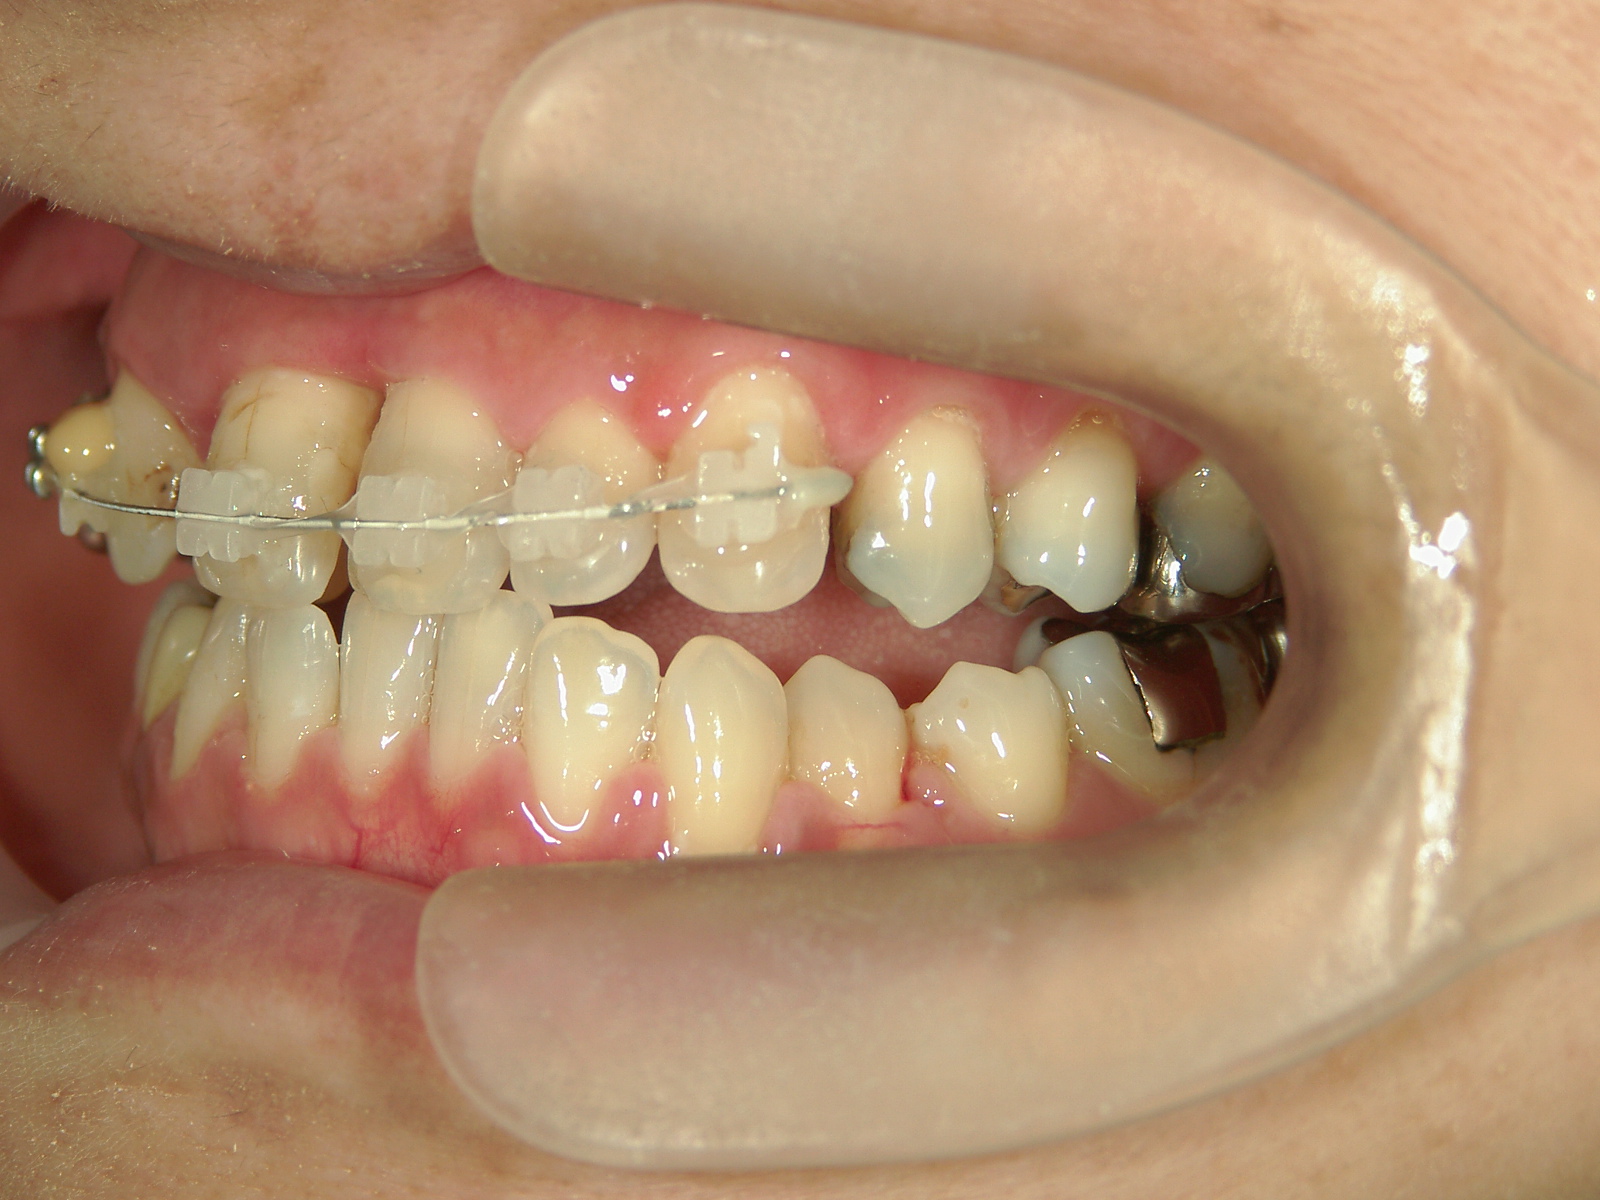

主訴: 受け口、歯並びが気になる。

右下第一小臼歯(1本)、右下親不知(1本)を抜歯。

右下第一大臼歯をセラミックへ変更。

上顎骨切断OPE、矯正装置(MSE+フェイスマスク)、ワイヤー矯正を併用。

①患者様はインビザライン矯正をご希望でしたが、上顎骨が小さく、受け口になっているので、インビザライン矯正で治療するために「骨切断OPE」「矯正装置(MSE+フェイスマスク)」で上顎骨を拡大しました。

②右上前歯が内側に入っているため、歯列に入る隙間を作るためにワイヤー矯正を併用し、右上前歯を出しました。